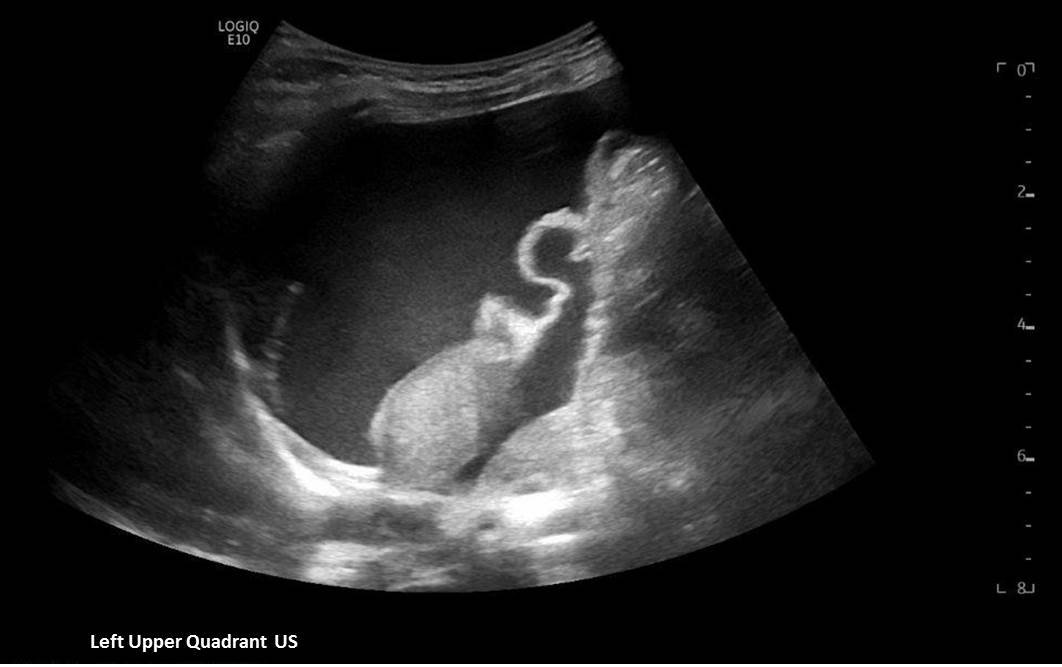

A 5-month-old female presented to the emergency department with worsening abdominal distention and postprandial emesis. Point-of-care ultrasound (POCUS) demonstrated extensive abdominal free fluid with a large, heterogeneous mass in the suprapubic region. This was confirmed on computed tomography (CT) of the abdomen and pelvis. The patient was urgently taken to the operating room for exploratory laparotomy where a ruptured tumor was discovered. The patient was eventually diagnosed with ovarian juvenile granulosa cell tumor. POCUS can be vital in guiding the recognition of rare pediatric conditions in the emergency department and should be considered in patients where there is concern for an acute abdomen.